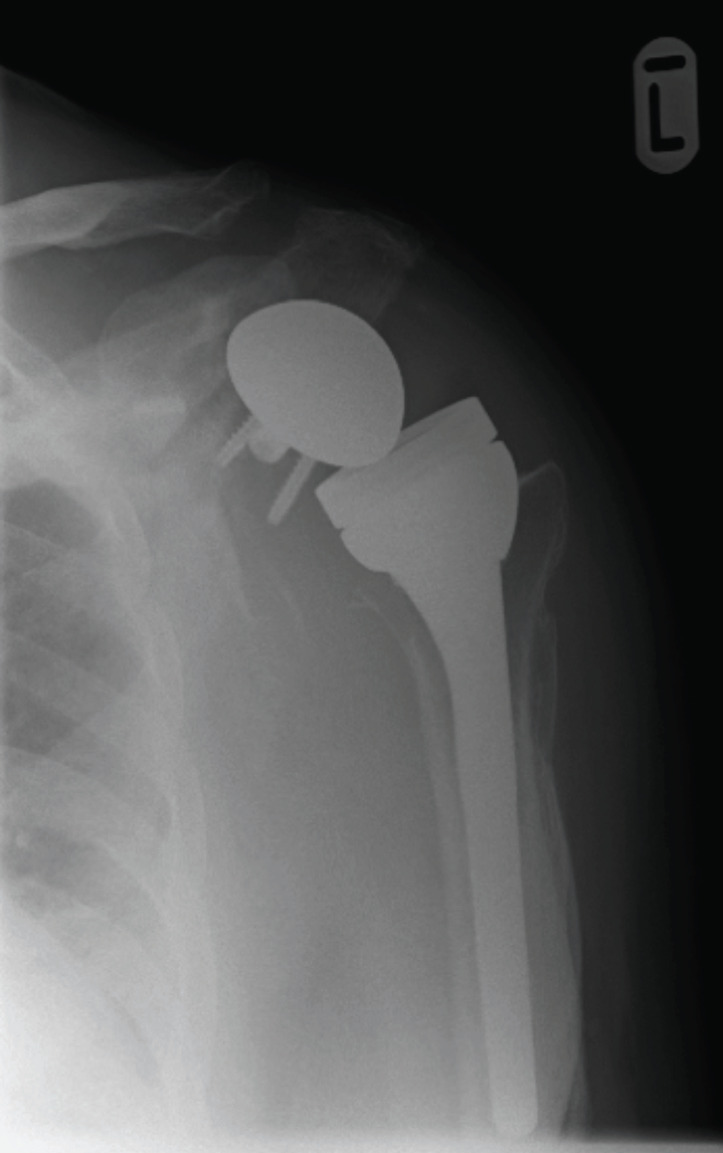

Abstract Image

Results: A total of 32 patients were identified with a mean age of 67.64 years and the most common cause of revision was a combination of bone and soft tissue failure (39.3%). All patients (n=8) with hemiarthroplasty had rotator cuff deficiency while patients with resurfacing had both rotator cuff failure and bony erosion. Four patients needed a proximal humeral osteotomy and six patients needed allograft reconstruction of the glenoid for bone loss. Twenty-one shoulders were revised to reverse total shoulder arthroplasty (TSA), 2 to anatomical TSA and 5 were left with cement spacer in situ. Mean duration of follow-up was 41.6 months. Mean OSS at the last follow-up was 26.88 with statistically significant improvement in ROM. There was no statistical difference in clinical outcomes (p>0.05) based on the type of primary prosthesis or cause of revision. A total of 70% patients were pain free. Patients with infection had inferior outcomes with a mean OSS of 17.